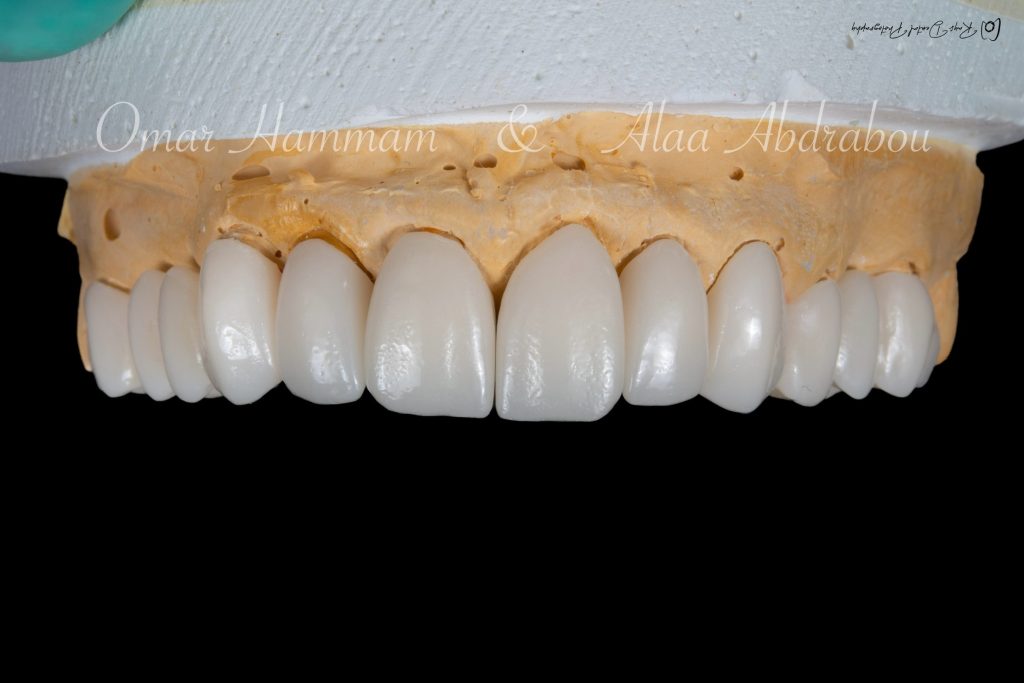

📔 𝑷𝒂𝒓𝒕 5 (𝑭𝒊𝒙𝒆𝒅 𝒑𝒓𝒐𝒔𝒕𝒉𝒐𝒅𝒐𝒏𝒕𝒊𝒄𝒔):

🔗 https://heyzine.com/flip-book/622184078c.html